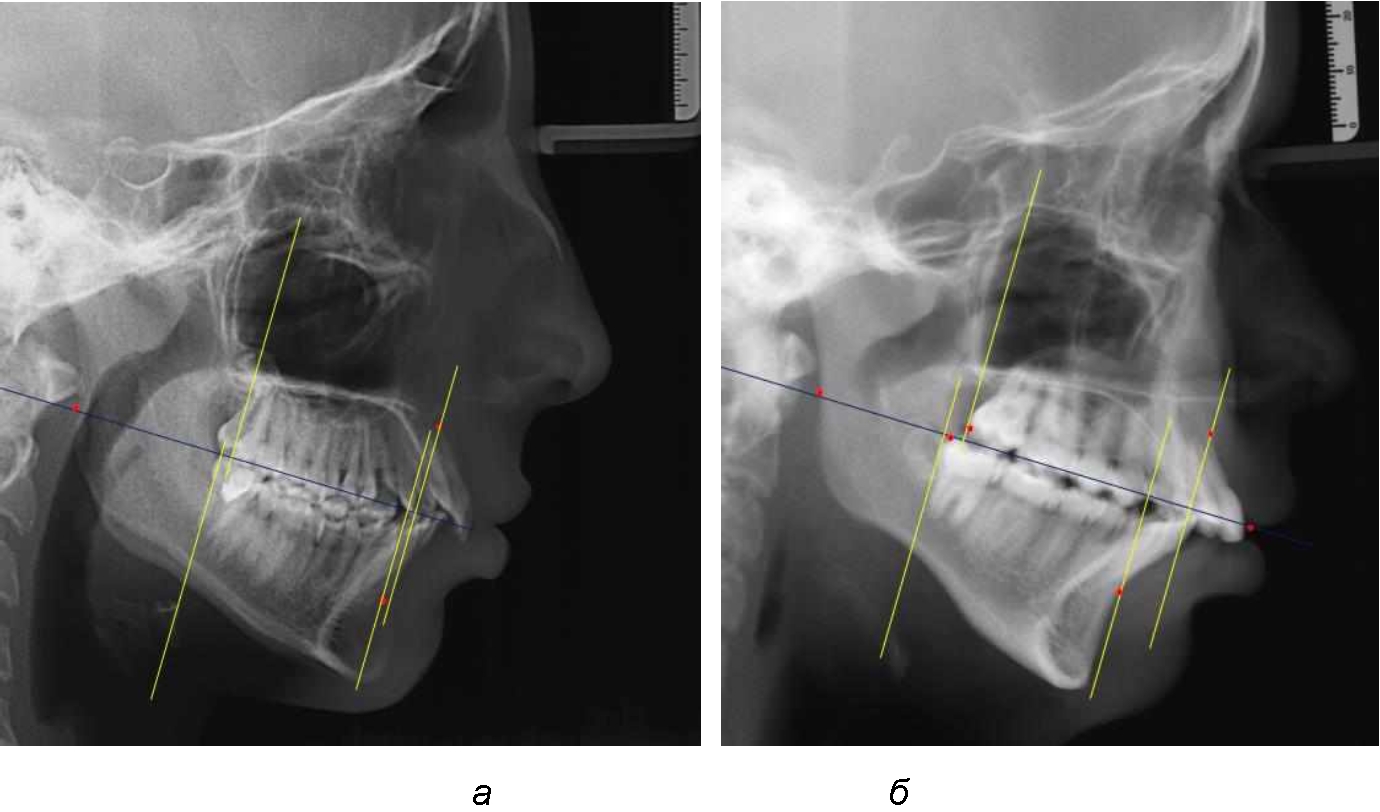

На рентгенограммах устанавливали точки Downs. На верхней челюсти субспинальная точка A(SS) располагалась в наиболее вогнутой точке альвеолярного отростка по переднему его краю. На нижней челюсти супраментальная точка B(SM) соответствовала месту наибольшей вогнутости переднего края альвеолярной части. Окклюзионную линию проводили через контактную точку резцов (vРOcP) и дистальную точку окклюзии второго нижнего моляра (hРOcP). Место пересечения окклюзионной линии с дистальным краем ветви нижней челюсти (ramus mandibule) обозначали как «rmРOcP». Перпендикулярно к окклюзионной плоскости проводили линии из точек «А(SS)» и «В(SМ)», что определяло их проекцию на окклюзионную линию. Аналогично отмечали положения дистальных окклюзионных точек верхней и нижней челюсти (рис. 1).

Рис. 1. Положение основных точек (а) и линейных ориентиров (б) для анализа положения и размеров челюстей

Альвеолярно-дентальный размер верхней челюсти и нижней челюсти оценивали по окклюзионной линии между вертикалями, ограничивающими исследуемые челюсти. Положение верхней челюсти оценивали по величине размера «rmOcP-А», а нижней челюсти по расстоянию «rmOcP-В». Линия смыкания губ обозначалась как точка «sto», вблизи которой проходила окклюзионная линия. Данный ориентир позволял провести окклюзионную плоскость при аномалиях положения резцов в вертикальном направлении, когда была сложность определения резцовой окклюзионной точки (vРOcP).